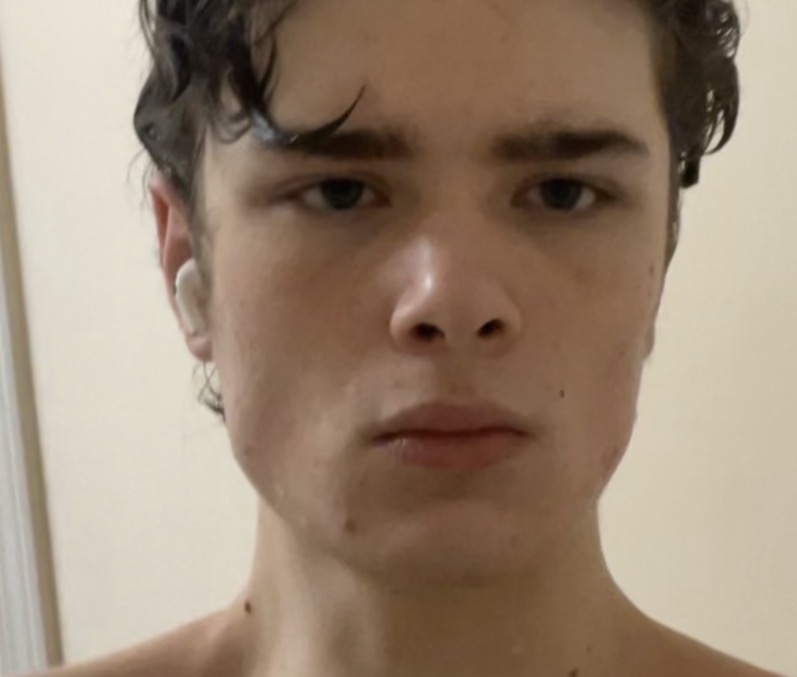

I know i have some level of crowding but i can’t tell if it’s mild or severe. I’m seriously considering getting some sort of orthodontic device (ex MARPE), i often have trouble breathing through my nose especially during workouts and my tongue overlaps my teeth slightly when pressed to my upper palate. Will orthodontics genuinely benefit me or is my case not severe enough?

Also when i smile 8 of my upper teeth show im not too sure what the golden number is but i’ve read it’s around 8-10.

Front: